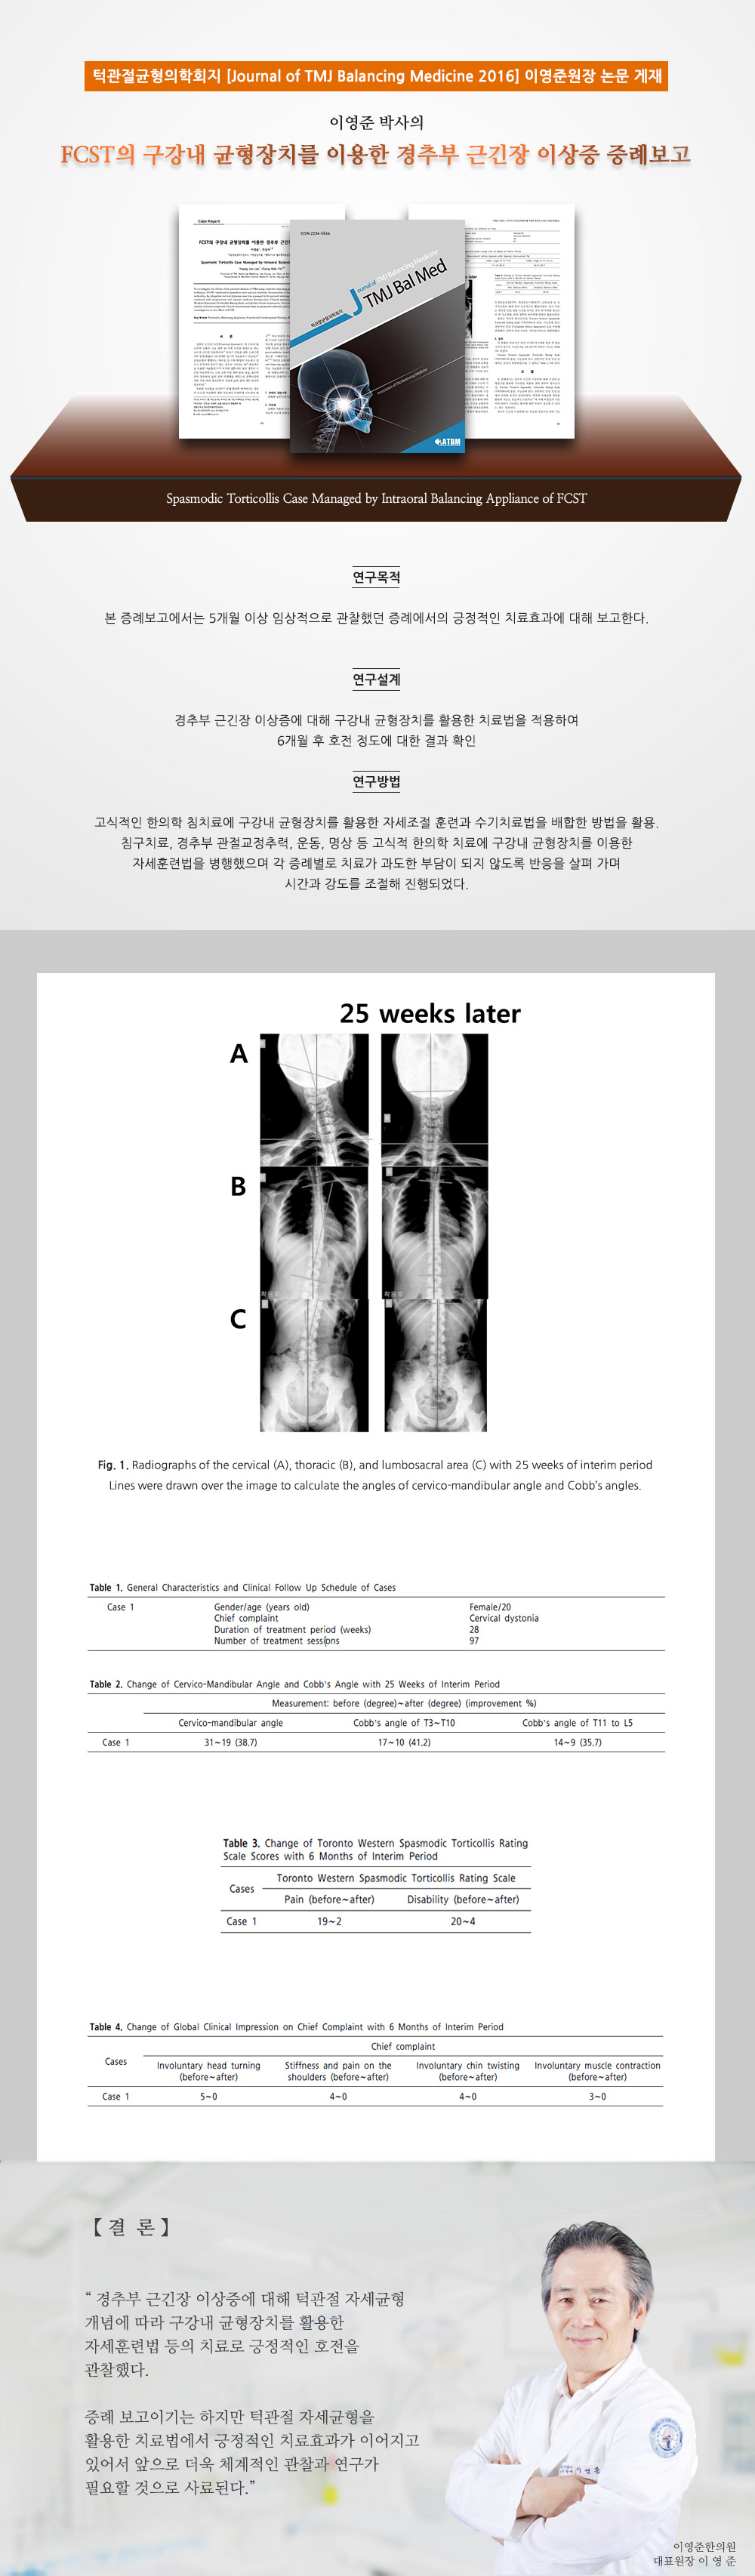

Á¦¸ñ 2016 FCSTÀÇ ±¸°­³» ±ÕÇüÀåÄ¡¸¦ ÀÌ¿ëÇÑ °æÃߺΠ±Ù±äÀå ÀÌ»óÁõ Áõ·Êº¸°í

ÀÛ¼ºÀÚ ÀÌ¿µÁØ ÇÑÀÇ¿ø